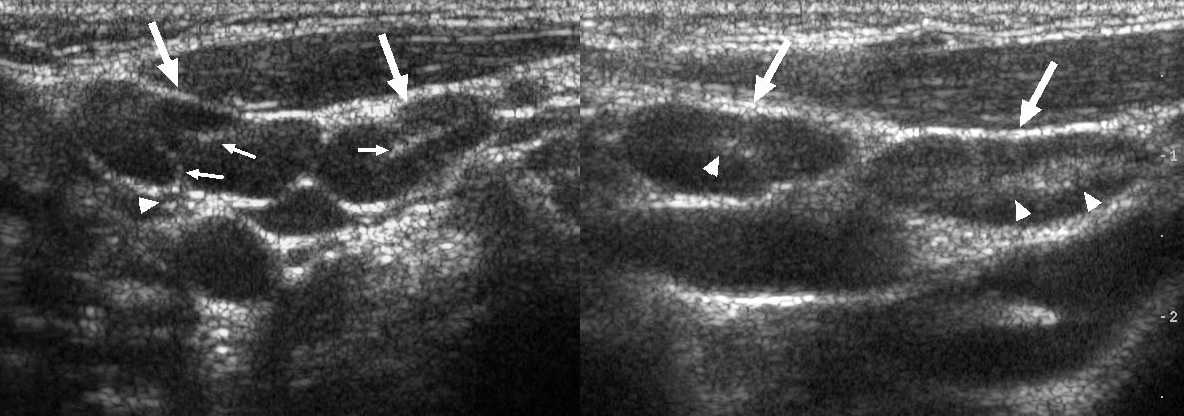

Вступая в борьбу с инфекцией лимфоузлы воспаляются. Воспалённые лимфоузлы стремительно «растут» в начале болезни и быстро «сдуваются» при выздоровлении. На УЗИ лимфоузел увеличен за счет корковой и околокорковой зоны, гипоэхогенный по периферии и гиперэхогенный в центре, форма овальная, контур четкий, кровоток только в воротах или отсутствует. Если воспаление переходит в окружающую клетчатку (периаденит), то может сформироваться абсцесс.

Рисунок. У детей с ОРВИ на УЗИ увеличенные шейные лимфоузлы с сохранной архитектурой — овальной формы, контур четкий и ровный, гипоэхогенные по периферии с гиперэхогенным центром. Заключение: Лимфаденопатия шейных лимфоузлов.

Рисунок. Мальчик 6-ти месяцев с выраженным дерматитом. На УЗИ шейные (1) и подчелюстные (2) лимфоузлы увеличены, вытянутой формы, гипоэхогенные по периферии с гиперэхогенной линейной структурой в центре

Обратите внимание подчелюстной лимфоузел с волнистым контуром. Заключение: Лимфаденопатия шейных и подчелюстных лимфоузлов